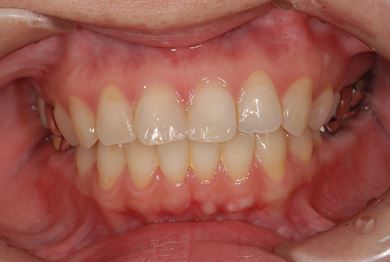

| 性別/年齢 | 女性 / 39歳 | ||||||||||||||||||||||||||||||||

| 主訴 | 右奥歯の虫歯と、右奥のインプラント治療について相談。 | ||||||||||||||||||||||||||||||||

| 治療方針 | 右下奥欠損部分をインプラント治療にて、機能的・審美的回復を行う。 | ||||||||||||||||||||||||||||||||

| 治療内容 | インプラント1本、ハイブリッドセラミッククラウン1本 | ||||||||||||||||||||||||||||||||

| 総治療費 | 329,963円 | ||||||||||||||||||||||||||||||||

| 治療期間 | 5ヶ月 |